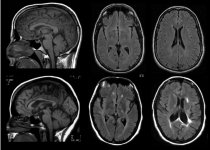

Кунио Накамуро и его коллеги из Монреальского неврологического института установили, что мозг человека уменьшается в течение дня, а на следующее утро его объем восстанавливается. Исследование основано на анализе почти 10.000 снимков магнитно-резонансной томографии мозга. Канадские ученые исследовали 3269 сканирований головного мозга в ходе испытаний с участием больных рассеянным склерозом, еще 6114 респондентов проекта страдали болезнью Альцгеймера. Что делает данное исследование крупнейшим в области неврологии.

Сравнивая снимки мозга одних и тех же испытуемых, но сделанные в разное время суток, неврологи обнаружили существенное увеличение объема мозга по утрам. У респондентов с рассеянным склерозом к вечеру мозг уменьшался на 0,18%, а у второй группы - на 0,44%. Для сравнения - примерно такая же степень сокращения объема мозга происходит у людей за год при развитии болезни Альцгеймера.